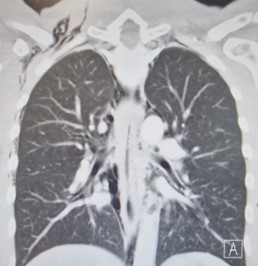

A chest X-ray performed (Figure 1) in the Emergency Department demonstrated significant subcutaneous emphysema. Subsequent computed tomography of the thorax showed extensive pneumomediastinum with a locule of intramural gas possibly reflecting a focal rupture point (Figure 2).

Figure 1: Chest X-Ray.